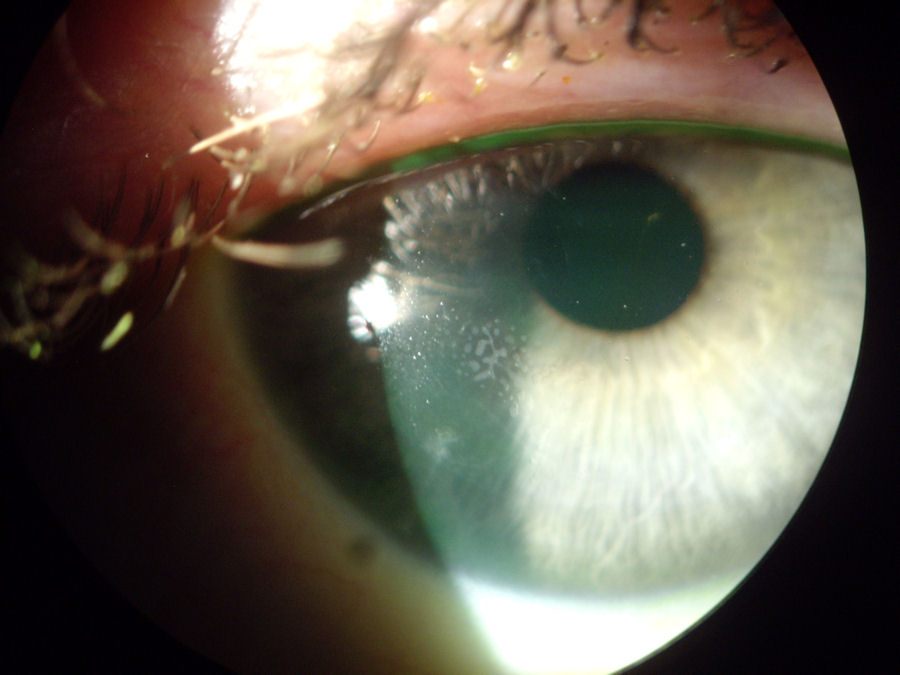

На фотографии ниже представлена роговица после операции LASIK с врастанием эпителия и эктазия . Инородный предмет, расположенный по периметру роговицы, представляет собой имплантируемую пластиковую вставку, называемую ПОТРЕБЛЯЕМЫЕ ВЕЩЕСТВА , который был имплантирован в попытке сгладить эктазию. Т-образный белый шрам в положении "9:00" - это разрез, который был сделан для введения Intacs в роговицу. Молочная полоса, проходящая с 7:00 до 8:00, - это врастание эпителия. Нажмите на изображение, чтобы увеличить.